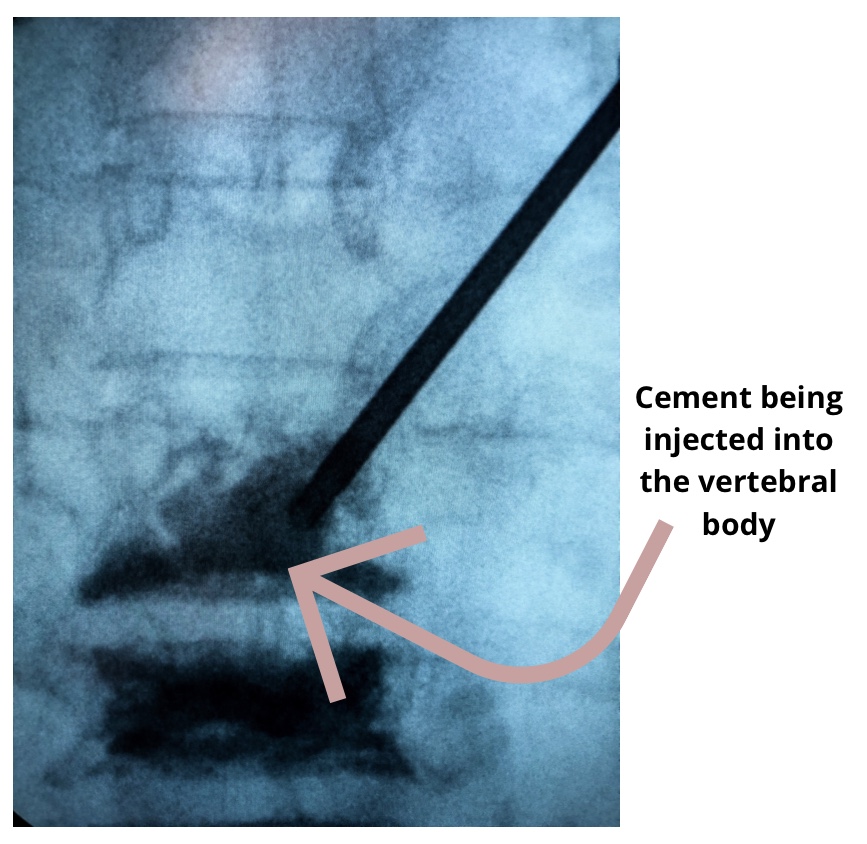

Kyphoplasty

As I’ve mentioned before, I am currently working as a medical assistant in pain management. It’s now been almost a month that I started my new job and I love it! I get to work alongside the best pain management doctors in my area and have learned so much in a short amount of time.…